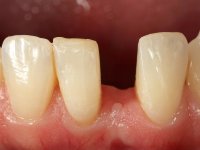

E

xtreme mobility of the deciduous tooth.

Female patient, 40 years old, non-smoker. Presented agenesis of tooth 31 with the presence of deciduous tooth 71.

After clinical and radiographic examination, two alternatives for the oral rehabilitation were proposed:

• orthodontic treatment to open the mesio-distal space to allow the placement of a dental implant and its crown;

• ‘Maryland bridge’, with a slight slice of adjacent teeth to allow the creation of a pontic with a mesio-distal diameter compatible with adjacent teeth.

Patient chose the second option.